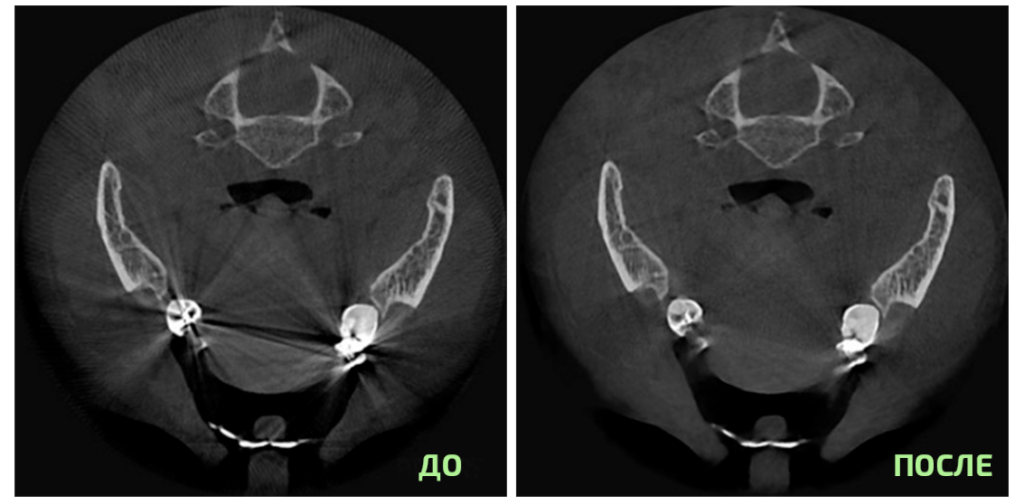

Улучшенная обработка изображений SMARF™

(функция подавления рентгеноконтрастности)

Существенно снижает “шум” от металлических конструкций, протезов и имплантатов для обеспечения оптимальной визуализации всех зон интереса.

Алгоритм SMARF: уменьшает искажения от металлов